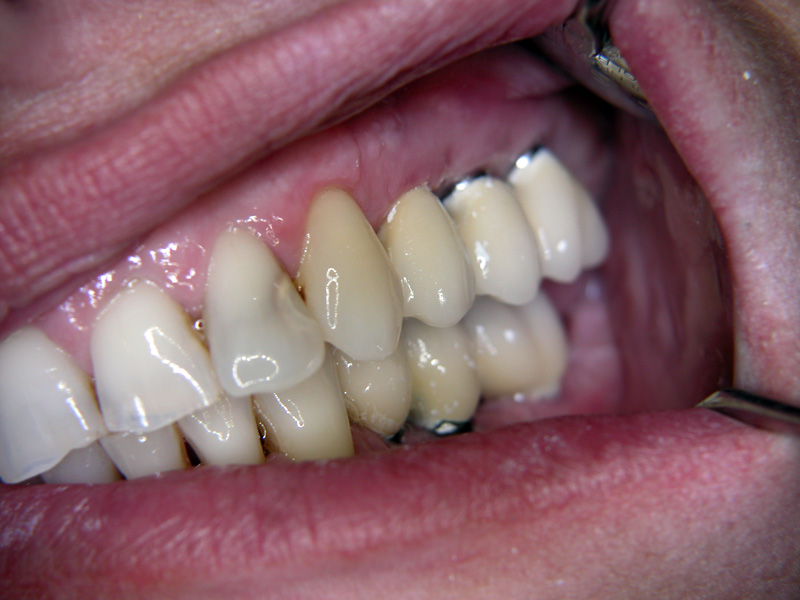

Implante - Galerie Foto

Caz IV